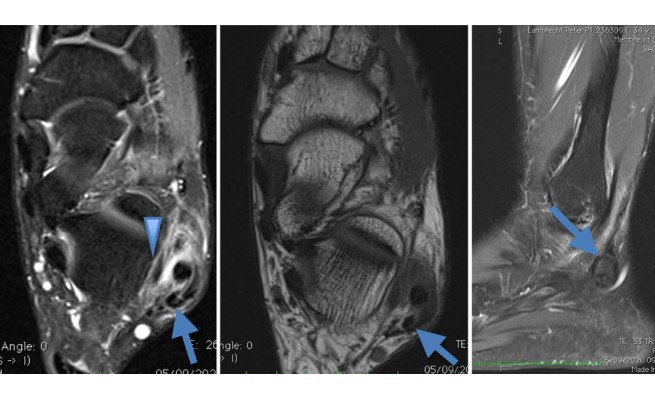

Tendon accessoire de type peroneus quartus

Les variantes anatomiques musculaires sont fréquentes, le plus souvent non symptomatiques et de découverte fortuite en imagerie. Ces variantes peuvent correspondre à un muscle surnuméraire ou accessoire, un muscle absent ou des variations de trajet ou d'insertion. Dans certains cas, les muscles accessoires sont responsables d'une masse palpable, parfois douloureuse et, dans ce cas, souvent à l'effort. Ils peuvent également comprimer les axes vasculo-nerveux (muscle anconé épithrochléen et compression du nerf ulnaire au coude par exemple).